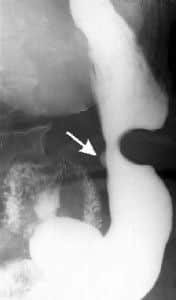

• ULCERA GÁSTRICA ANGULAR

•  ULCERA DUODENAL

• ESTENOSIS DISTAL AL BULBO Y NICHO ULCEROSO